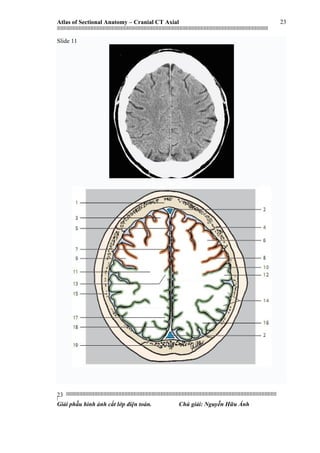

Slide 11

1. Frontal bone

2. Superior sagittal sinus

3. Superior frontal gyrus

4. Coronal suture

5. Falx cerebri

6. Middle frontal gyrus

7. Longitudinal cerebral fissure

8. Precentral sulcus

9. Precentral gyrus

10. Central sulcus

11. Cerebral whitematter (semioval center)

12. Postcentral gyrus

13. Paracentral lobule

14. Supramarginal gyrus

15. Parietal bone

16. Inferior parietal lobule

17. Precuneus

18. Parieto-occipital sulcus

19.Occipital bone

1. Xương trán

2. Xoang tĩnh mạch dọc trên

3. Hồi trán trên

4. Khớp vành

5. Liềm não

6. Hồi trán giữa

7. Khe dọc tiểu não

8. Rãnh trước trung tâm

9. Hồi trước trung tâm

20. Rãnh trung tâm

11. Chất trắng (trung tâm bán bầu dục)

12. Hồi sau trung tâm

13. Thuỳ cạnh trung tâm

14. Hồi trên viền

15. Xương đỉnh

16. Thuỳ chẩm dưới

17. Trước chêm

18. Rãnh chẩm

19. Xương chẩm